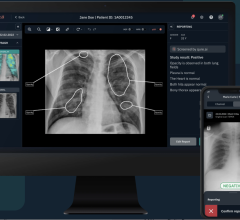

The Society of Cardiovascular Computed Tomography (SCCT) annual meeting July 10-13 in San Diego covered the latest CT trends, technology and clinical trial data. The key takeaway message was that CT technology is advancing rapidly and there is a strong feeling cardiac CT may be able to become a one-stop-shop imaging test, eliminating the need for diagnostic catheterizations, nuclear perfusion scans, stress tests and others used to diagnose chest pain or disease progression. In this regard, experts at SCCT said CT could become a primary gatekeeper to the cath lab for percutaneous coronary intervention (PCI) procedures, and help eliminate the high percentage of diagnostic caths performed on patients with normal or non-obstructive disease.

A key component of this transformation is a new super-computing technology called CT-fractional flow reserve (FFR), which may offer a noninvasive alternative to catheter-based FFR, the current gold standard for determining if a stent is required for a particular lesion. Experts at SCCT said this, combined with CT myocardial perfusion imaging, will be more accurate and help eliminate the need for nuclear perfusion imaging.

Other key topics included ways to decrease CT dose, and evaluations of CT cost-effectiveness compared to use of several other tests and length of stay.